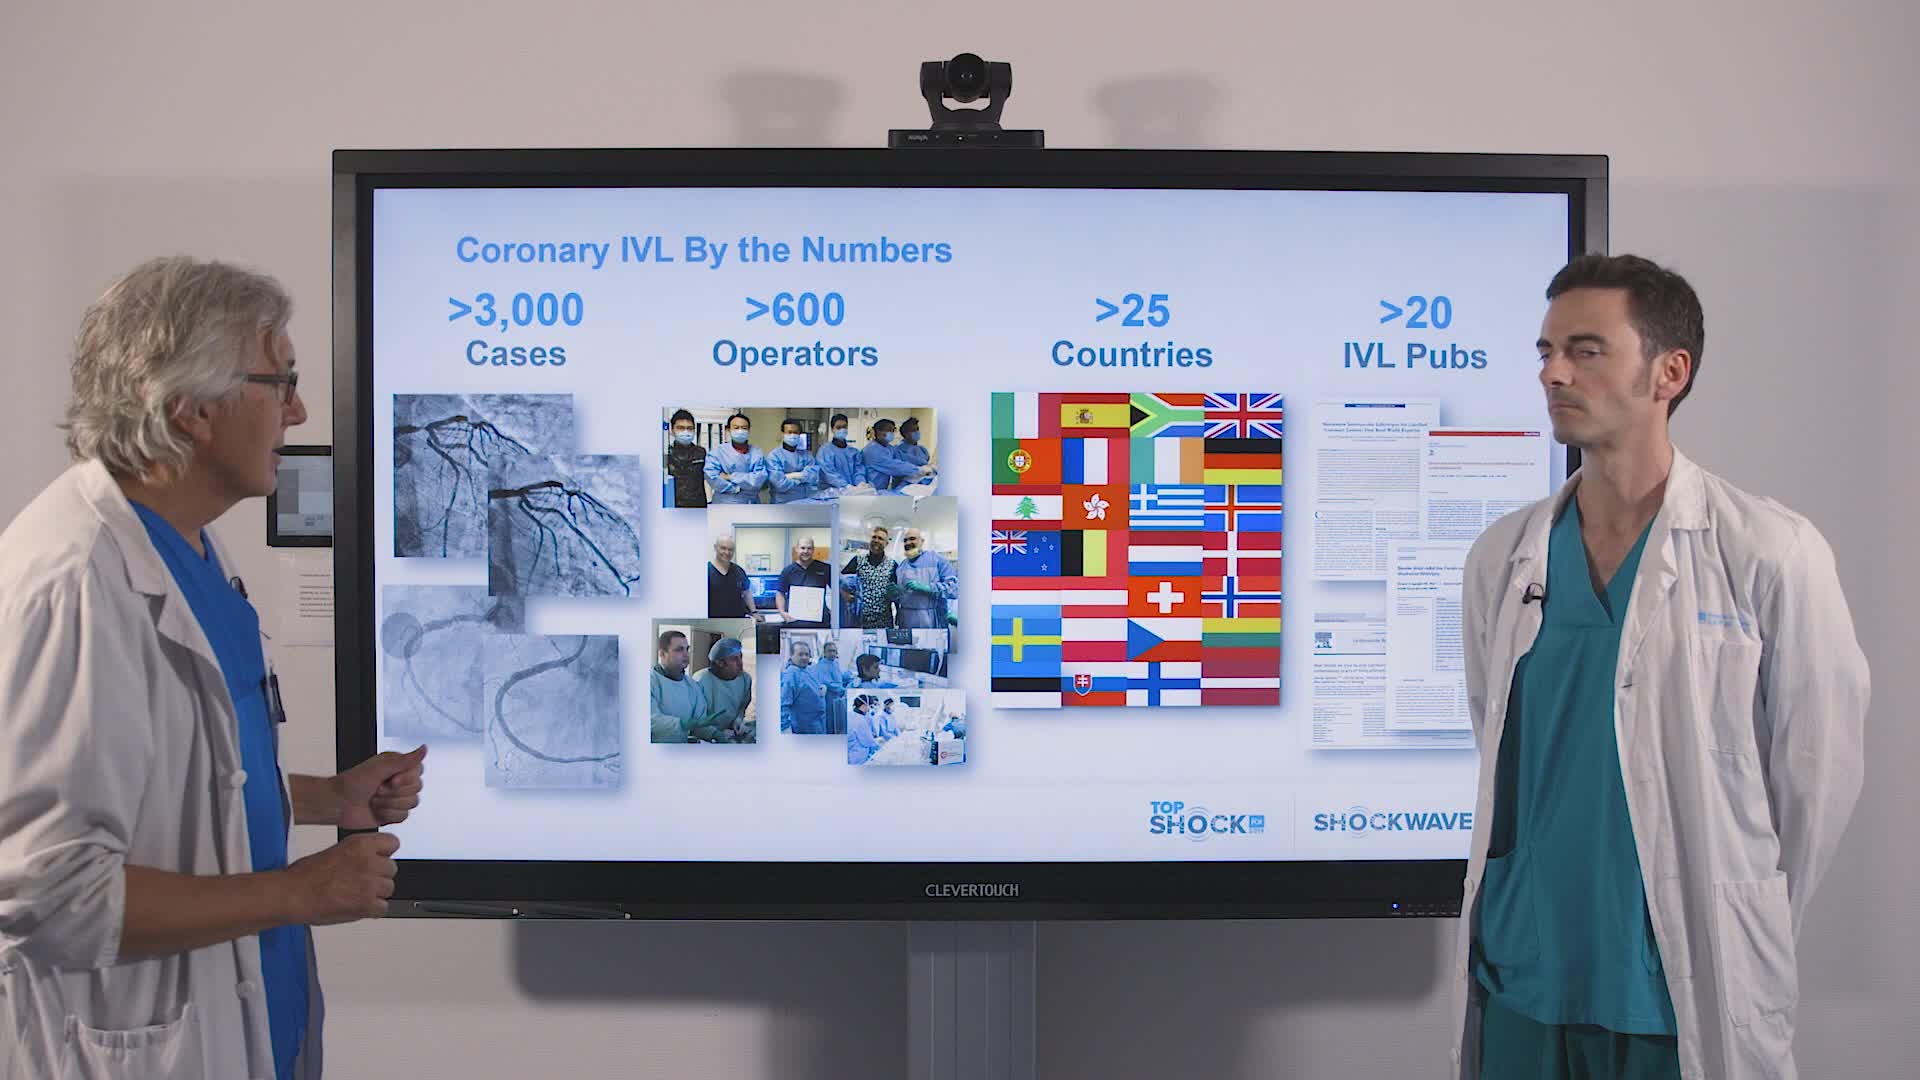

Coronary IVL Greatest Hits

Real-World EU Experience: Coronary IVL Across Different Calcium Morphologies from TCT 2022

Intravascular Lithotripsy for Treatment of Severely Calcified Coronary Artery Disease: The Disrupt CAD III Study

Shockwave IVL Coronary Real-World Cases, Outcomes & Algorithms: An InCathLab Webinar